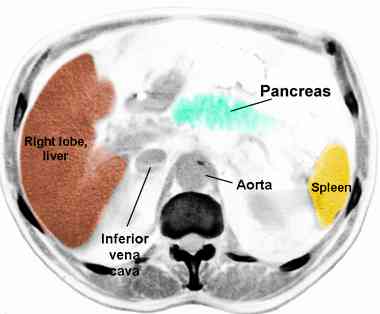

CT anatomy: a, b, c, d, e, f , g,  hi, j      CT anatomy more: a, b, c , de f, more      CT pancreas cancer from JHU